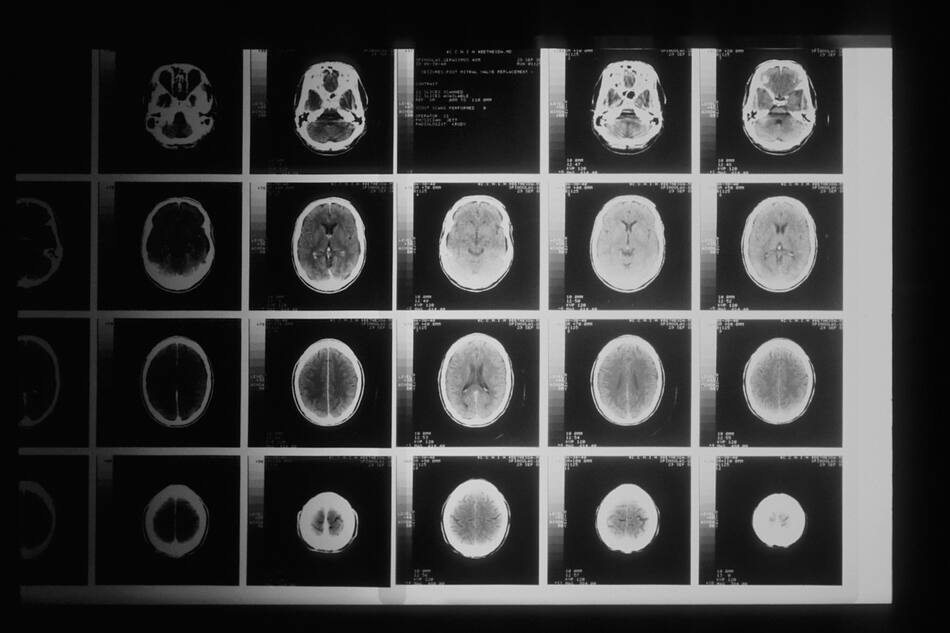

Estudian un modelo de inteligencia artificial que ayuda a determinar el origen de los tumores. Foto: Unsplash.